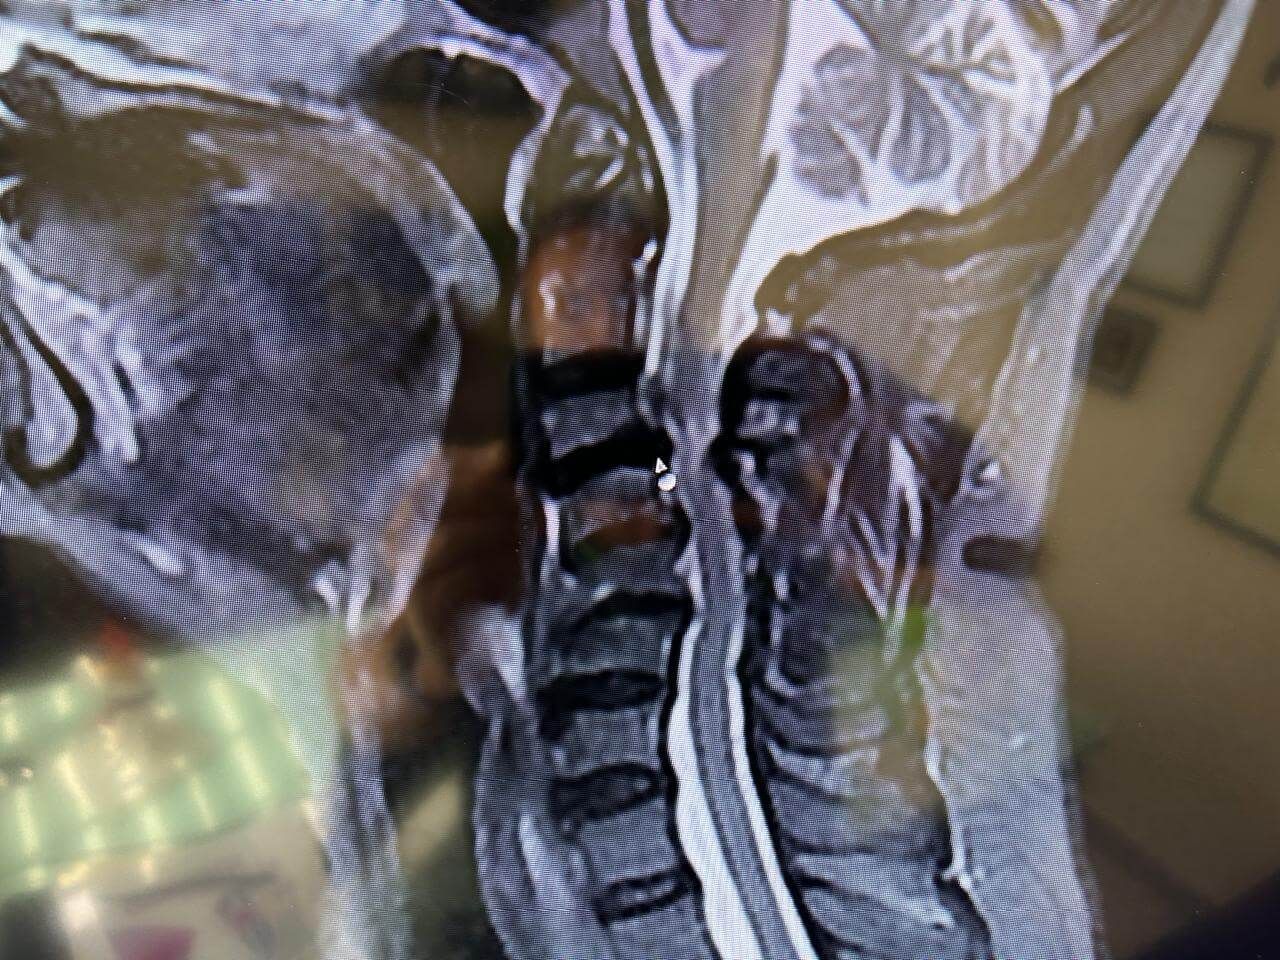

Cirugía de mínima invasión de columna vertebral

Realiza cirugías endoscópicas mínimamente invasivas de columna.

Ofrece diagnósticos y tratamientos especializados para la columna vertebral.

Cirugía de Columna

Realiza cirugía habitual y endoscópica mínimamente invasiva de columna vertebral.